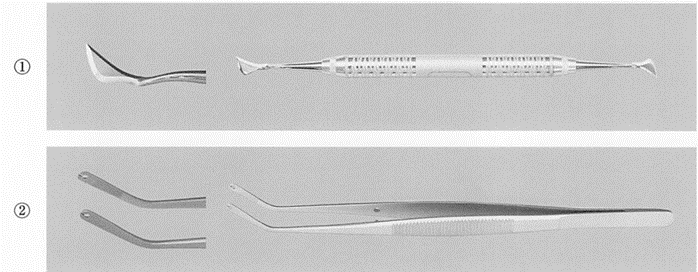

器具の写真を別に示す。 歯肉切除術に使用するのはどれか。2つ選べ。

a. ①

b. ②

c. ③

d. ④

解答を見る

a.d